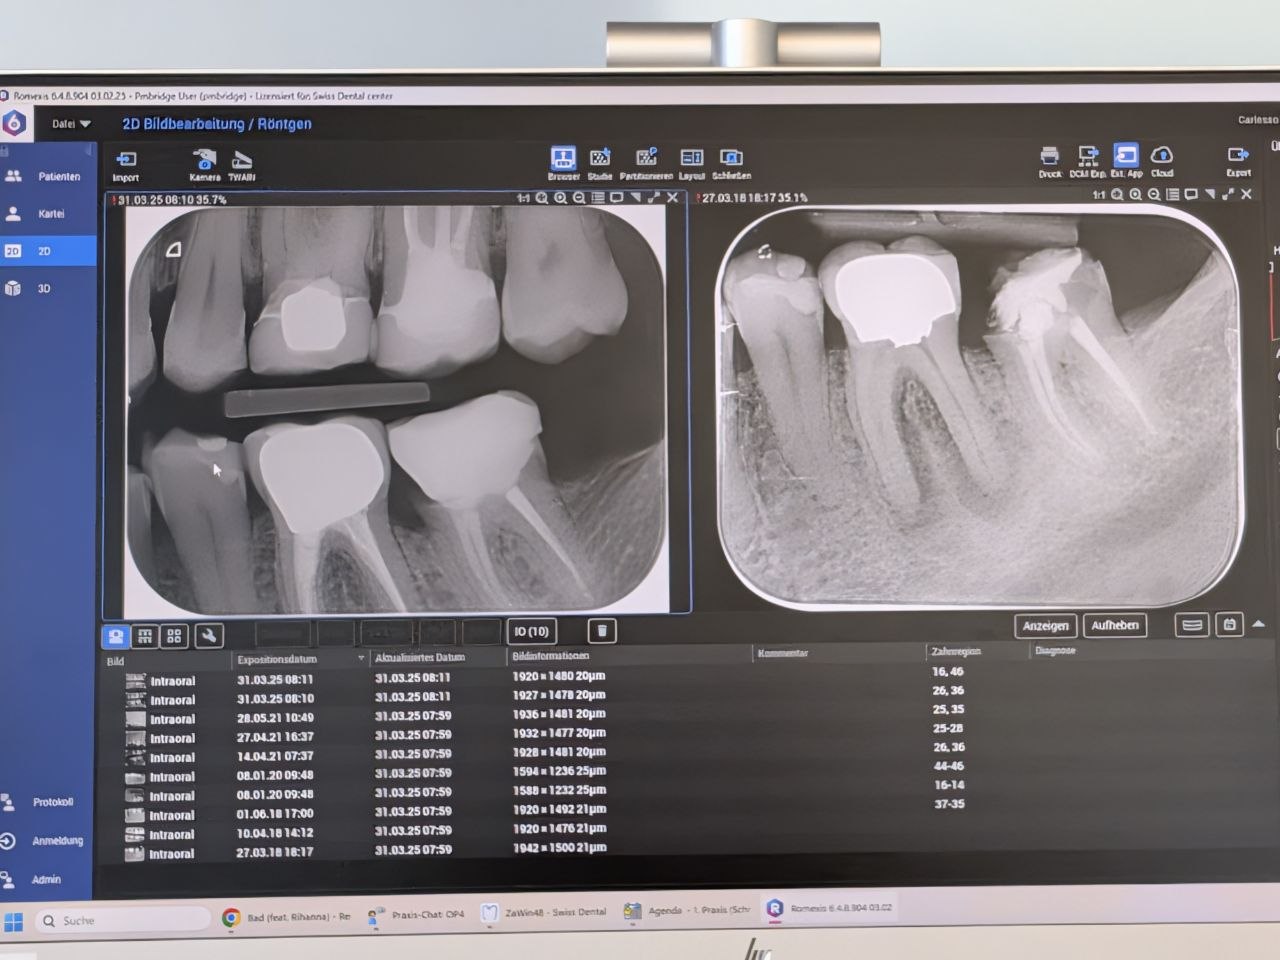

Later, I went to the dentist to fix a tooth that broke while I was in South Africa eating sushi. It wasn’t just a small chip; the entire crown (€2,000) and the underlying amalgam core buildup came off. What’s left of the original tooth is minimal, basically just the root from a root canal.

Here’s the X-ray showing the situation:

The dentist rebuilt the core (€300) and we’ve scheduled the new crown for Monday, May 4th, 2026.